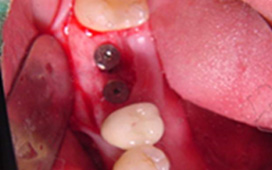

單顆雙植體 案例一